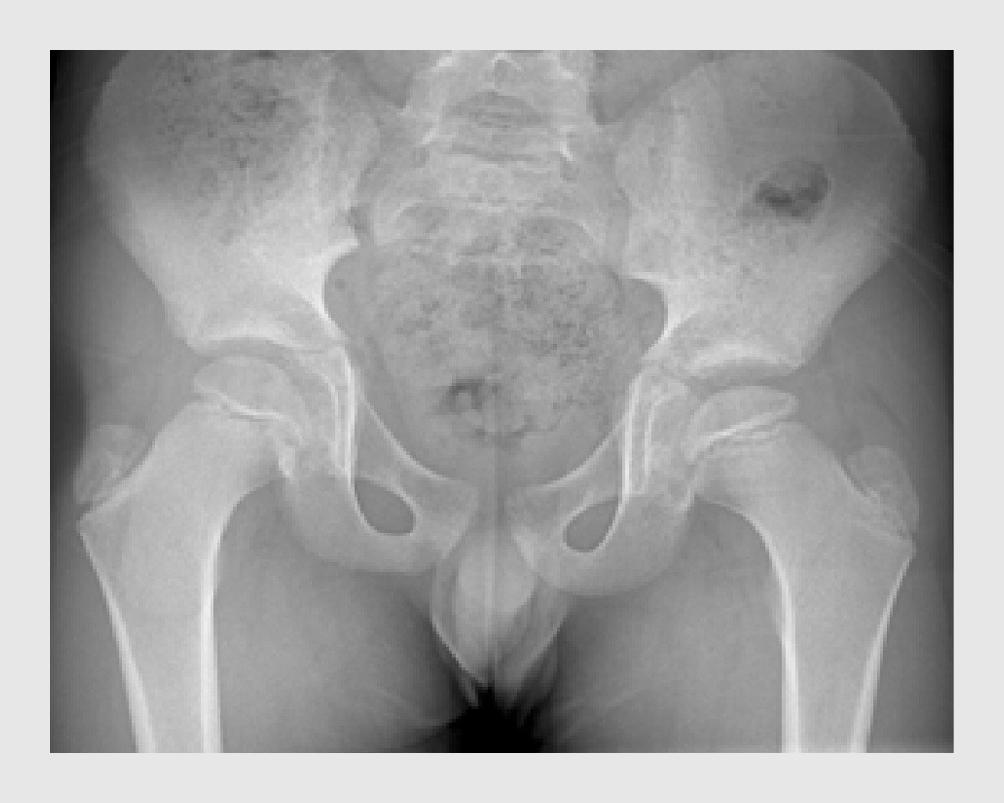

Patiënt D is een 12-jarige jongen die de huisarts bezocht, omdat hij sinds een aantal weken pijn in de linker lies ervoer. Patiënt had een opvallend mankend looppatroon, waarbij hij zijn linker been ontzag. Bij lichamelijk onderzoek was endorotatie van de linker heup beperkt. Hij had geen koorts. De huisarts liet röntgenopnames van het bekken maken, inclusief een anteroposterieure en een Lauenstein-opname (figuur 4). De radioloog beoordeelde deze beelden als niet afwijkend, waarop de huisarts de diagnose ‘tendomyogene klachten’ stelde.

Progressie van de epifysiolyse van het caput ossis femoris bij een 12-jarige jongen

Figuur 4 | Progressie van de epifysiolyse van het caput ossis femoris bij een 12-jarige jongen

Röntgenfoto’s van beide heupgewrichten laten progressie zien van de epifysiolyse van het caput ossis femoris in de loop van 6 maanden. (a) Anteroposterieure röntgenfoto ten tijde van eerste presentatie, waarop geen afwijkingen zichtbaar zijn; de lijn van Klein loopt beiderzijds door de epifyse. (b) De gelijktijdig vervaardigde Lauenstein-opname toont een subtiel afgegleden epifyse van het caput ossis femoris. (c) Op de röntgenfoto 6 maanden later is duidelijk sprake van epifysiolyse van het caput ossis femoris; de lijn van Klein ligt beiderzijds buiten de epifyse. (d) De Lauenstein-opname na 6 maanden bevestigt de epifysiolyse aan beide kanten, links meer dan rechts.

Een half jaar later verwees de huisarts patiënt alsnog naar de poli Kinderorthopedie, omdat de pijn toenam en nu in beide liezen aanwezig was. Er was geen sprake van koorts. Bij lichamelijk onderzoek zagen wij een jongen die mank liep met zijn linkerbeen in exorotatie. Zowel bij extensie van de heup in buikligging als bij 90° flexie van de heup, waren beide heupen 10° geëxoroteerd en was er geen endorotatie mogelijk. Bij passieve flexie van de heupen trad spontane exorotatie van de geflecteerde heup op (het Drehmann-teken), wat gezien kan worden bij epifysiolyse van het caput ossis femoris, ‘hinge abduction’ of osteoartritis van het heupgewricht. We lieten nieuwe röntgenopnames maken, waarop nu beiderzijds epifysiolyse van het caput ossis femoris te zien was (zie figuur 4). In retrospect waren hier linkszijdig al tekenen van zichtbaar op de eerste Lauenstein-opname.

Wij schreven bedrust voor en opereerden patiënt de volgende dag, waarbij beiderzijds de epifyse van het caput ossis femoris werd gefixeerd middels percutane schroeven. Postoperatief moest patiënt 6 weken mobiliseren met krukken. Bij poliklinische controle na 1 jaar had patiënt een blokkadegevoel van de linker heup bij bukken en was er in beide heupen maximaal 10° endorotatie mogelijk. Het Drehmann-teken was beiderzijds aanwezig. Herhaalde röntgenopnames lieten de bekende standsafwijking van het caput ossis femoris zien, met een geringe sclerose van het acetabulum beiderzijds (figuur 5).

Figuur 5 | Operatief gefixeerde epifyse van het caput ossis femoris

Röntgenopnames van het bekken. (a) Anteroposterieure opname 1 jaar na schroeffixatie van het caput ossis femoris beiderzijds. (b) Gelijktijdige Lauenstein-opname.